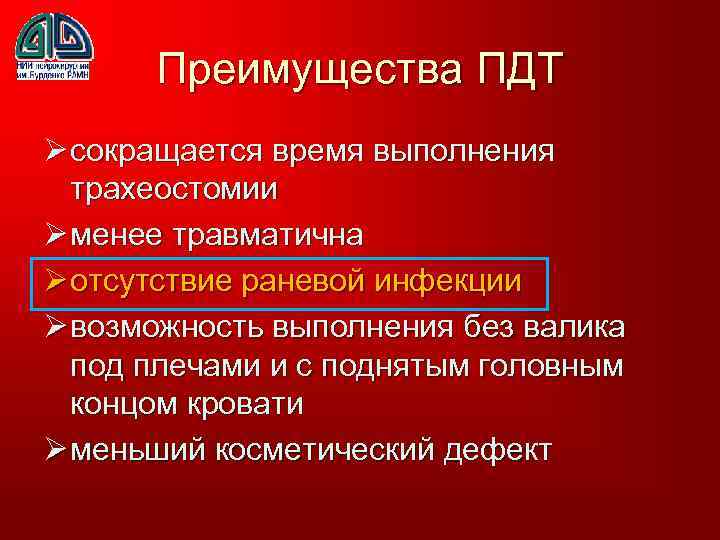

Преимущества ПДТ Ø сокращается время выполнения трахеостомии Ø менее травматична Ø отсутствие раневой инфекции Ø возможность выполнения без валика под плечами и с поднятым головным концом кровати Ø меньший косметический дефект

Преимущества ПДТ Ø сокращается время выполнения трахеостомии Ø менее травматична Ø отсутствие раневой инфекции Ø возможность выполнения без валика под плечами и с поднятым головным концом кровати Ø меньший косметический дефект

Преимущества ПДТ Ø сокращается время выполнения трахеостомии Ø менее травматична Ø отсутствие раневой инфекции Ø возможность выполнения без валика под плечами и с поднятым головным концом кровати Ø меньший косметический дефект

Преимущества ПДТ Ø сокращается время выполнения трахеостомии Ø менее травматична Ø отсутствие раневой инфекции Ø возможность выполнения без валика под плечами и с поднятым головным концом кровати Ø меньший косметический дефект